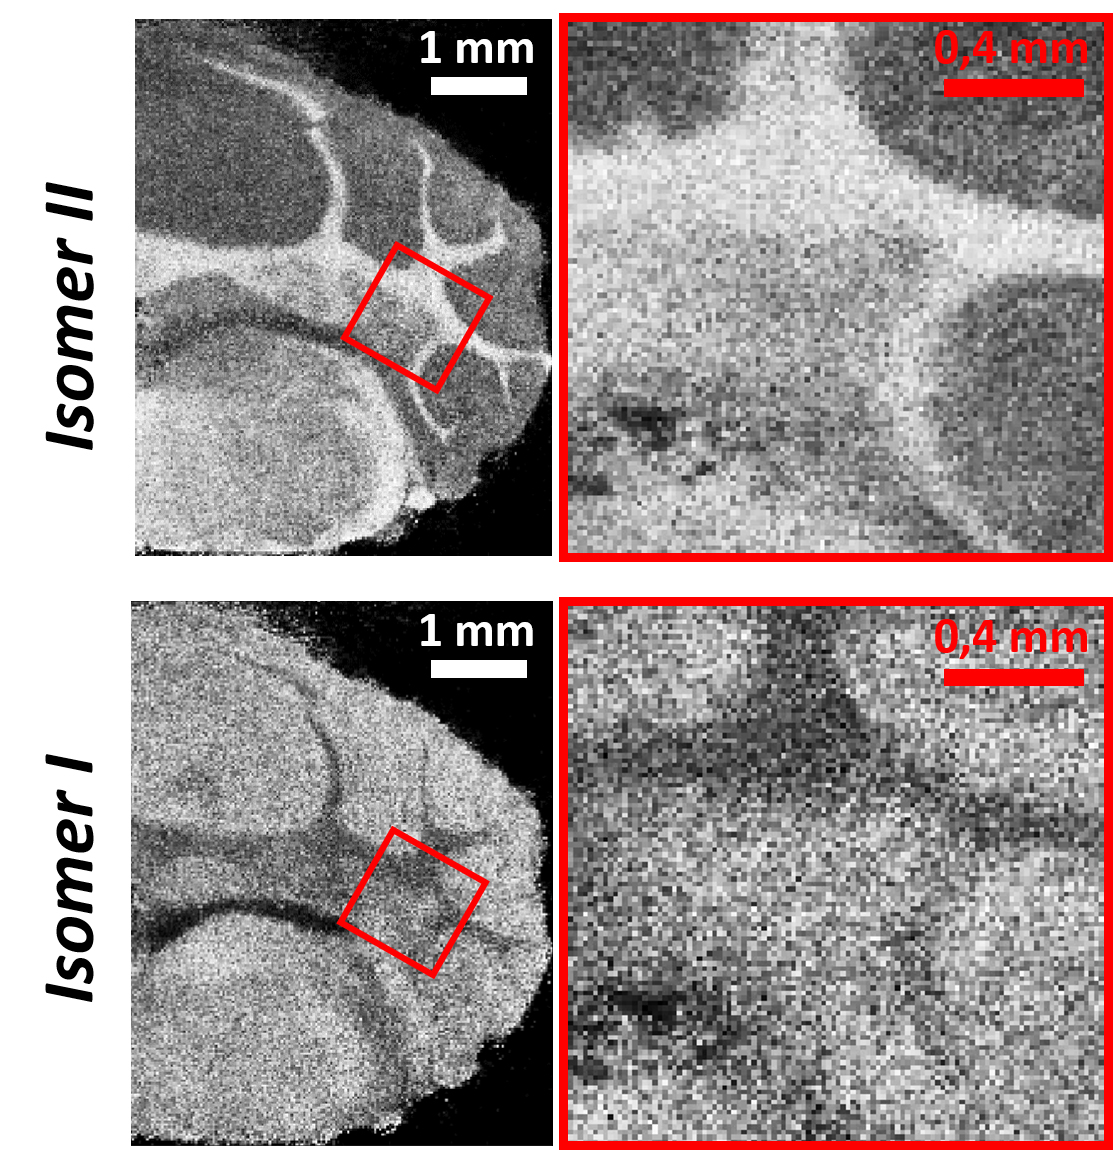

Das in der Nachwuchsgruppe von Dr. Sven Heiles am Institut für Anorganische und Analytische Chemie der JLU entwickelte Messprinzip „Reactive MALDI“ nutzt einen fokussierten Laserstrahl, der ortsgenau sehr geringe Substanzmengen aus dem untersuchten Gewebe verdampft und gleichzeitig eine chemische Reaktion zwischen den Stoffwechselprodukten (Metaboliten) und einem Hilfsstoff („Matrix“) initiiert. Die dabei entstehenden Ionen werden in einem Massenspektrometer detektiert, wodurch eine Vielzahl von Verbindungen unterschieden und zusätzlich strukturelle Unterschiede von sogenannten Isomeren – Moleküle mit der gleichen Anzahl und Art an Atomen, die sich nur hinsichtlich ihrer räumlichen Struktur unterscheiden – erkannt werden können. Im Anschluss an die massenspektrometrischen Analyse liefert das Abrastern der Probenoberfläche mit Laserstrahlung mikroskopische Bilder, die Informationen über die Stoffzusammensetzung, die Mengen und die chemischen Strukturen enthalten.

Neben Parasiten haben die Gießener Forscherinnen und Forscher auch neuronale Zellen in Maushirngewebe untersucht, das häufig als Modell in neurologischen Studien zu Nervenkrankheiten verwendet wird. „Wir konnten nun erstmals die strukturellen Unterschiede von Stoffwechselprodukten auf zellulärer Ebene nachweisen“, erklärt Fabian Wäldchen, der als Doktorand an der Entwicklung der Methode beteiligt war. „Dieses eindrucksvolle Beispiel verdeutlicht die wahre Komplexität und Spezifität von Stoffwechselprozessen“, so Prof. Dr. Bernhard Spengler. „Das neue analytisch-chemische Verfahren ist ein erster wichtiger Schritt, um auch strukturelle Details von Metaboliten räumlich verfolgen und dadurch Stoffwechselprozesse sehr viel besser verstehen zu können.“